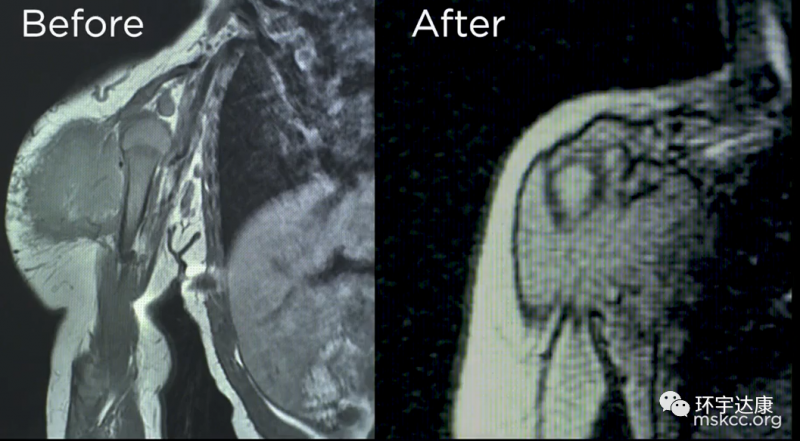

01、婴儿纤维肉瘤:拉罗替尼让巨大肿瘤在3天内消退

但是另Anna夫妇震惊的是,三天后,蕾哈娜(Rihanna)的巨大肿瘤就以肉眼可见的速度迅速缩小,他们带着蕾哈娜(Rihanna)来到医院,医生们也惊呆了!他们从未见过药物起效的速度如此之快。肿瘤已经长了几个月了,然而,一周内就快速消退了!

五个月后,外科医生来会诊后,高兴的告诉他们,如果肿瘤没有缩小,手术会影响蕾哈娜(Rihanna)的手臂功能,甚至需要截肢,导致她无法正常生活,但是现在肿瘤已经缩小了,可以通过手术将肿瘤完全切除,并且不会影响她日后的生活。

手术非常顺利,蕾哈娜(Rihanna)剩余的所有肿瘤都被切除,并且胳膊的功能没有收到任何影响。现在她已经快4岁了,医生说她已经完全没有肿瘤的迹象。